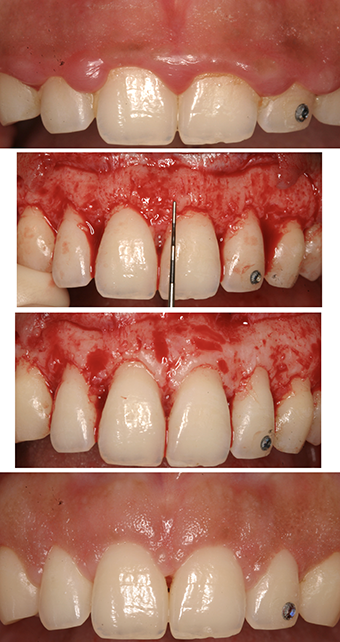

Apically positioned flap surgery with osseous resection (see Figure 2) is generally indicated when the alveolar bone crest is located closer than 3mm to the desired gingival margin. This approach allows direct visualization of the underlying bone architecture and facilitates precise bone removal. Osseous resection may include osteoplasty (which reshapes non-supporting bone) and ostectomy (which involves the removal of supporting bone directly associated with the tooth via the periodontal ligament). The primary objective of this procedure is to reposition the supracrestal tissue attachment more apically, thereby increasing clinical crown height while maintaining periodontal stability.